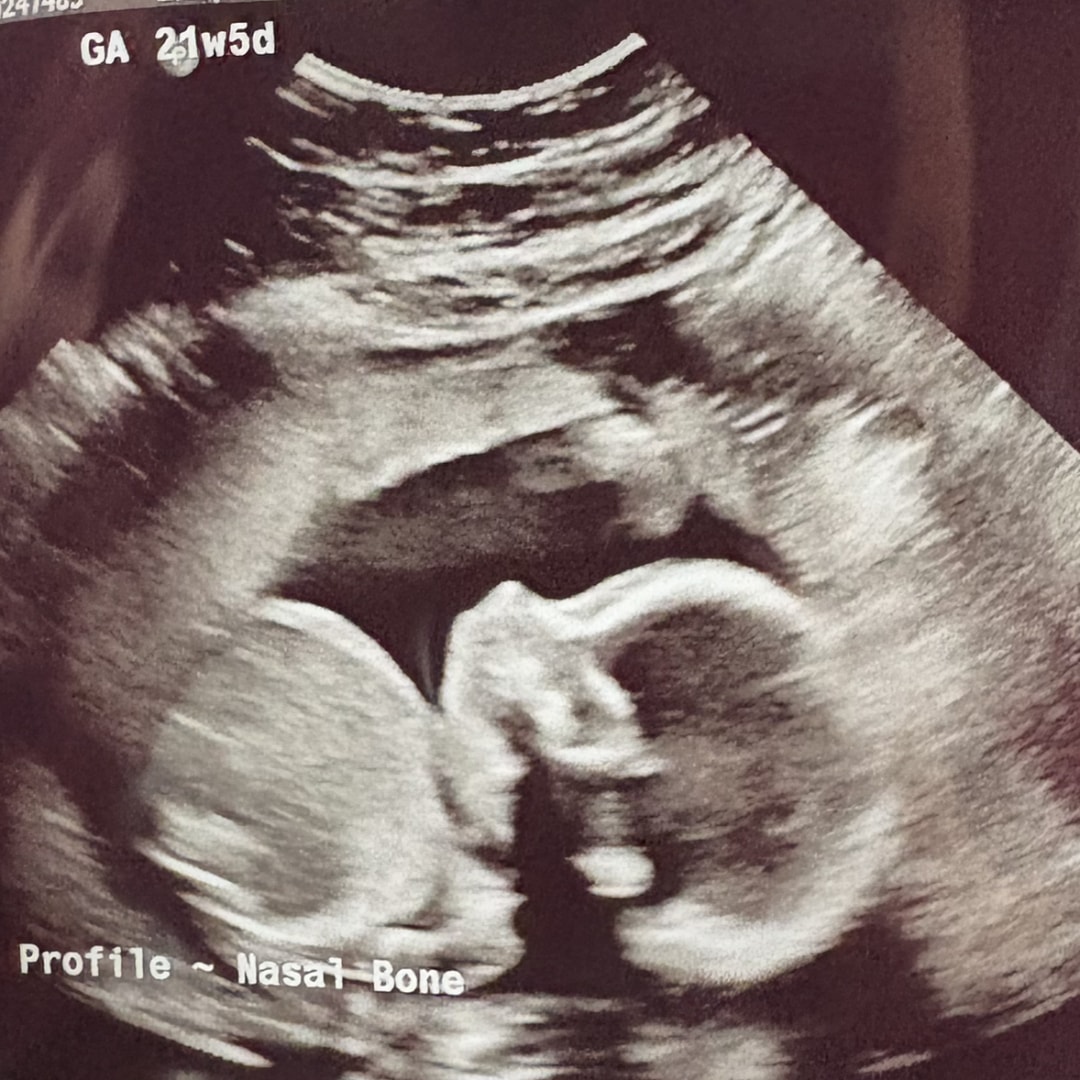

Andrew and I are so excited to welcome a baby boy in April. Thanks in advance for your help and support as we kick off this next adventure!

Baby Boy Lipniskis!